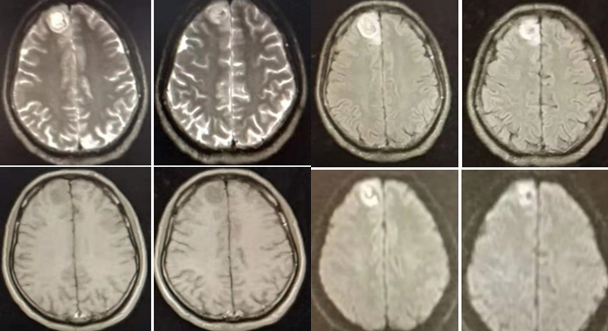

wernicke脑病影像

wernicke脑病影像表现